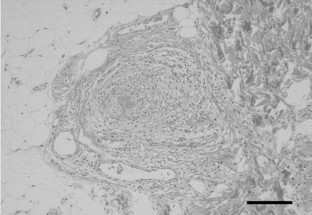

A 24-year-old Japanese woman was admitted for investigation of recurrent spiking high fever associated with a macular eruption of the upper extremities associated with fever and polyarthralgia. These symptoms were self-limiting but recurrent and seemed to be consistent with a diagnosis of adult-onset Still's disease (AOSD). However, livedo reticularis was detected on the lower extremities, suggesting the presence of vasculitic disease rather than AOSD. Investigation did not reveal any evidence of visceral involvement. Skin biopsy of the affected lower extremity demonstrated a necrotizing vasculitis of small muscular artery and confirmed a diagnosis of cutaneous polyarteritis nodosa (PAN) rather than AOSD. Treatment with 30 mg of prednisolone daily improved the skin lesions and the recurrent spiking high fever and the arthralgia were resolved. PAN and AOSD are clinically similar, and discrimination may be sometimes difficult. The presence of livedo reticularis and the finding of a characteristic skin biopsy appearance may be diagnostically useful to distinguish PAN from AOSD. Indeed, the clinical features of cutaneous PAN may be more similar to AOSD than systemic PAN, and a skin biopsy may be necessary to distinguish cutaneous PAN from AOSD in some cases.

Fig. 1